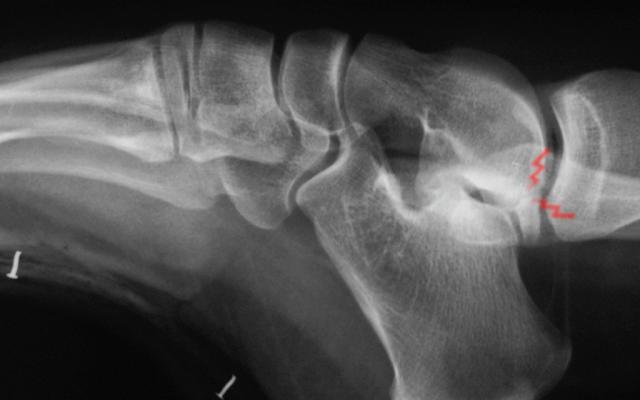

Full medial facet subtalar coalition

20 year old woman